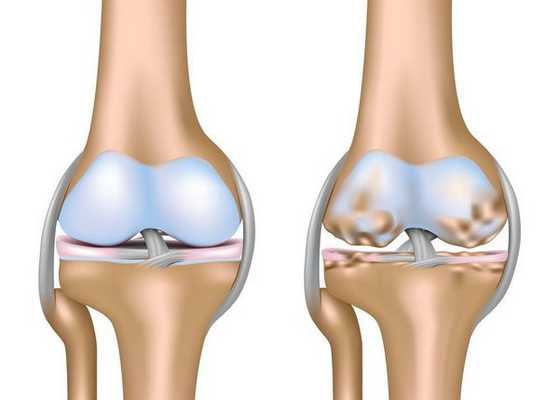

Остеоартроз (по международной классификации - остеоартрит) (ОА) - гетерогенная группа заболеваний различной этиологии со сходными биологическими, морфологическими, клиническими проявлениями и исходом; для лечения ОА наряду с противовоспалительной терапией применяется хондропротективная терапия [1]. При ОА страдают все структуры сустава: гиалиновый хрящ, субхондральная кость, синовиальная оболочка, параартикулярный аппарат. Воспаление проявляется прежде всего синовитом, который хорошо определяется клинически и при УЗИ суставов, что представлено на рисунке 1.

В норме при УЗИ суставной хрящ мало отличим от синовиальной жидкости. Здоровый гиалиновый хрящ анэхогенен, гомогенен, имеет четкие контуры, что представлено на рисунке 2.

При прогрессировании ОА суставной хрящ представляет собой неоднородную структуру с нормо- и гиперэхогенными включениями, хорошо видимыми во время УЗИ и представленными на рисунке 3. В последующих стадиях ОА при УЗИ определяется истончение гиалинового суставного хряща.

Современные возможности имплантатов синовиальной жидкости при остеоартрозе

Рис. 1. Переднее поперечное сканирование коленного сустава на уровне верхнего заворота. Хорошо видна анэхогенная гомогенная синовиальная жидкость в верхнем завороте (длинная стрелка) и утолщенная синовиальная оболочка (короткая стрелка)

Рис. 2. Нормальный хрящ надмыщелка бедренной кости (показан стрелкой)

Рис. 3. Суставной хрящ при гонартрозе (отмечен стрелкой). Изменения по типу хондрокальциноза (показан стрелкой)